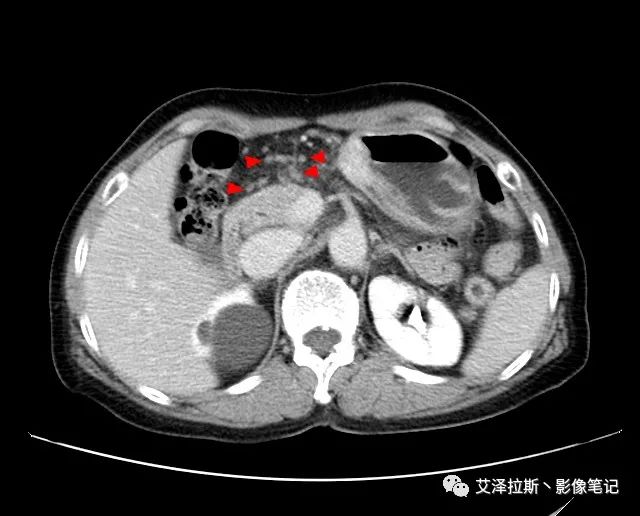

圖1 平掃+增強(qiáng)各期

【影像所見】 胃竇部狹窄,胃壁環(huán)形增厚,小彎側(cè)見一巨大潰瘍,周圍伴“環(huán)堤征”,漿膜面不完整,胃周脂肪見網(wǎng)格狀條索影,病灶與肝臟左葉、胰腺鉤突脂肪間隙消失,增強(qiáng)掃描病灶明顯強(qiáng)化。引流區(qū)內(nèi)約15個區(qū)域淋巴結(jié)受累。

【診斷意見】 胃竇部胃癌(T4N3期) 該病例腫塊突破漿膜層,與肝臟左葉、胰腺鉤突分界不清,脂肪界面消失,定為T4期; 受累及的淋巴結(jié)為15個區(qū)域,定為N3; 有無遠(yuǎn)處轉(zhuǎn)移尚不明確,所以M期暫時無法確定。